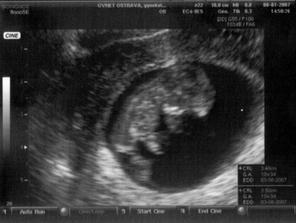

SRPŇÁTKA 2007 - fotky UTZ

album věnované mimískům, které se narodí v srpnu 2007 a jejich maminkám ze "Společného termínu SRPEN"